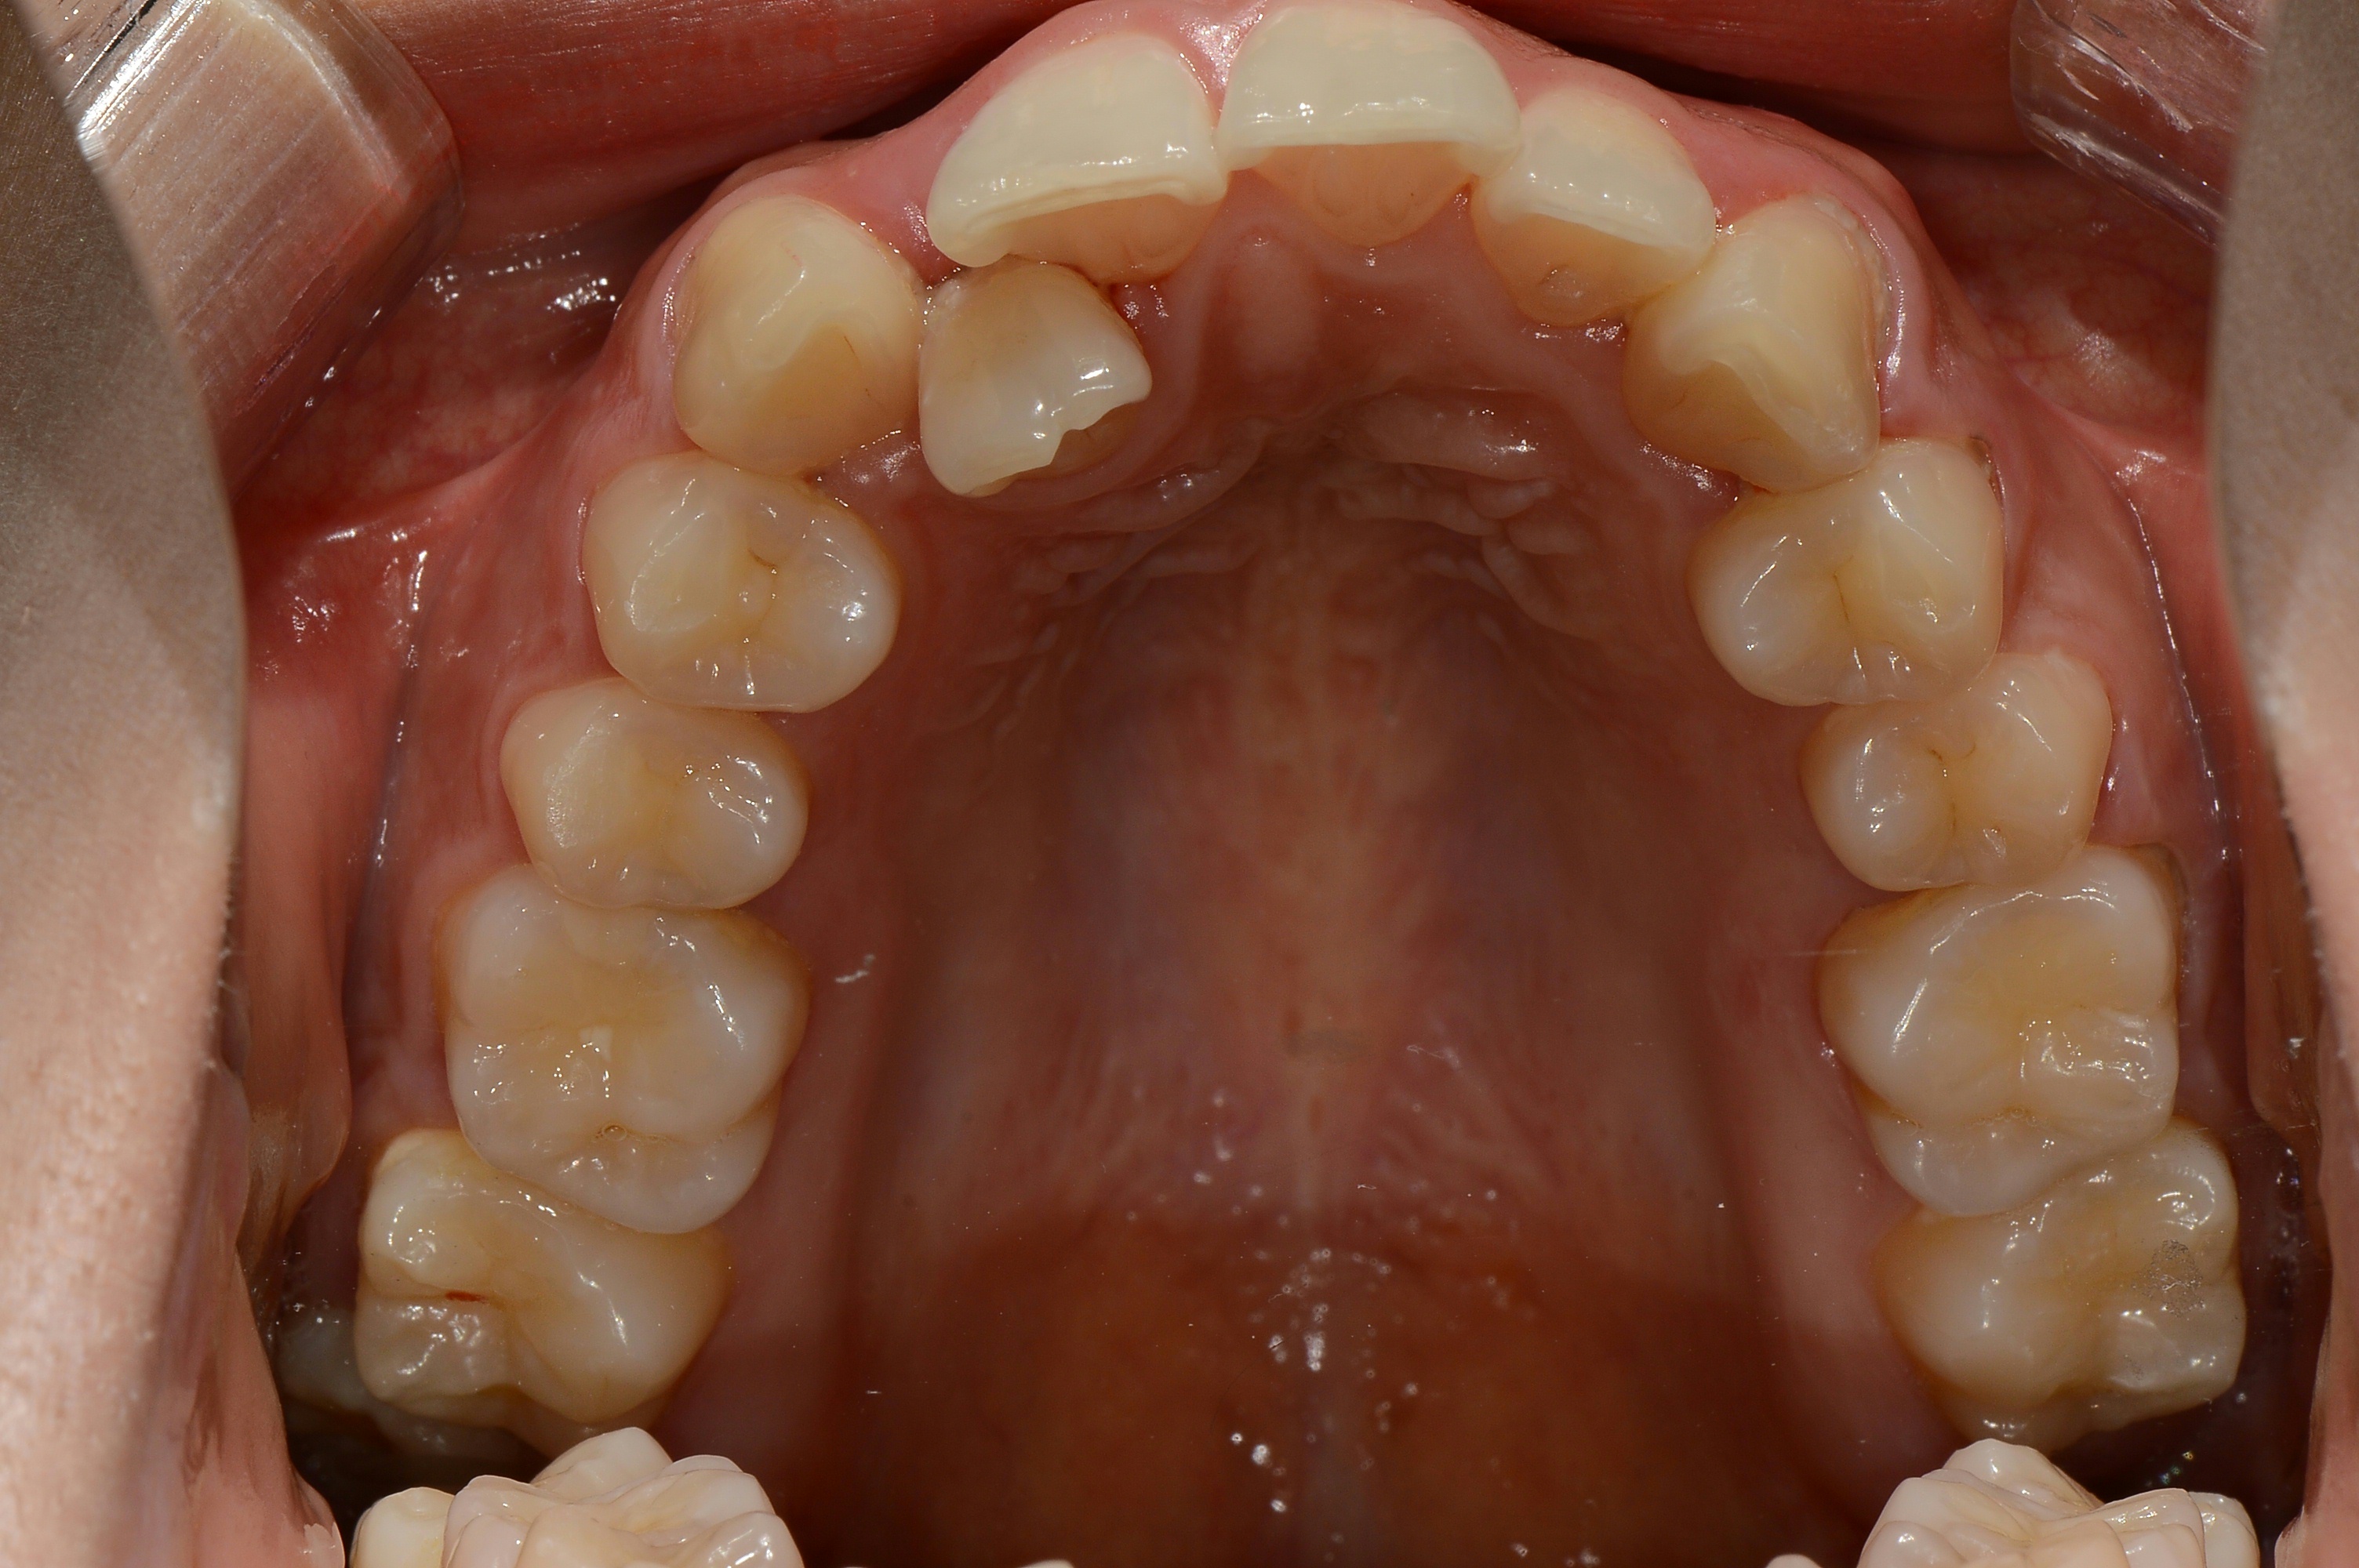

치료 후 사진입니다.